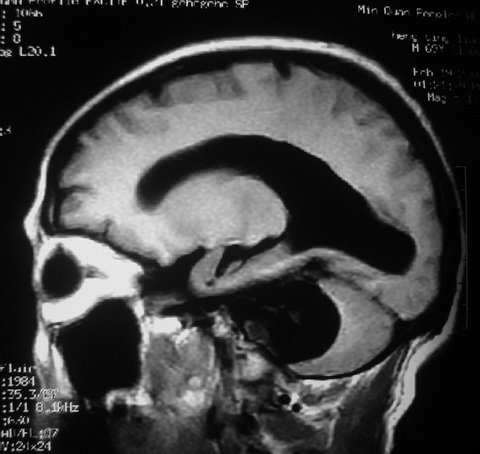

m,72,头疼,头晕两年,伴视力模糊三月,饮食呛咳两天。pe:颈部抵抗,左眼突出,左眼瞳孔约3mm,对光反射消失,双眼失明,伸舌困难,双肺呼吸音粗,心率110次/分,左上肢肌力i级,左下肢屈曲,肌张力高。现有08年2月19mri平扫及10年2月8日mri增强请会诊。ct病灶呈低密度伴散在点、片状等密度区,无明确钙化(无ct片资料可供上传)。[

[本贴已被 jiajie 于 2010-2-8 23:30:48 修改过]